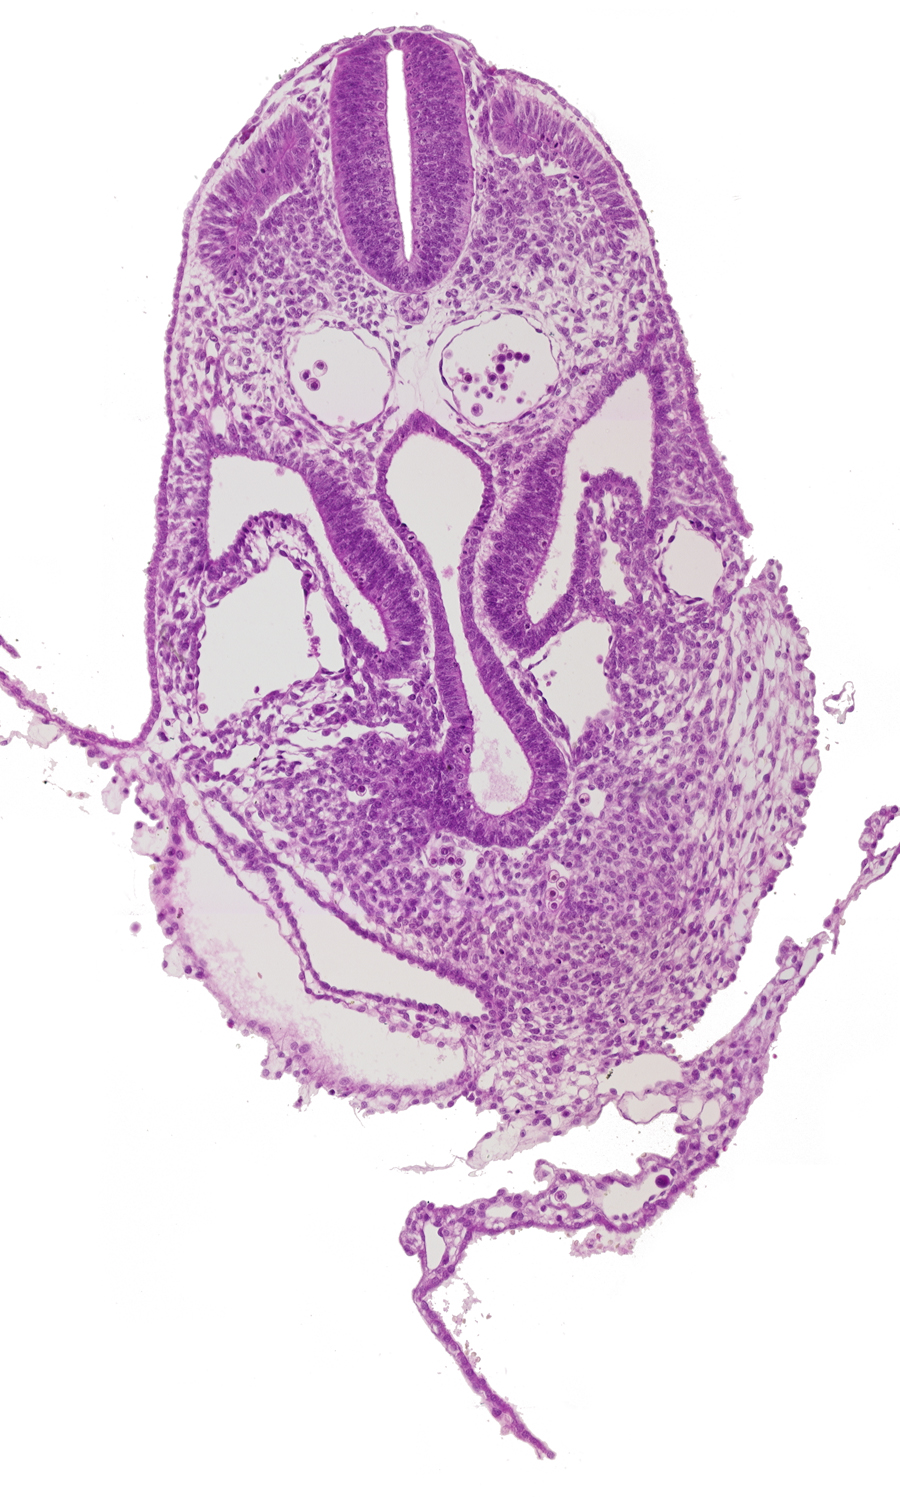

amnion, amnion attachment to ventral body wall, amniotic cavity, caudal part of pericardial cavity, dermatomyotome 6 (C-2), hemopoietic tissue, hepatic venous plexus, left umbilical vein, left vitelline (omphalomesenteric) vein, midgut, postcardinal vein, right horn of sinus venosus, sclerotome, umbilical vesicle wall

Carnegie Embryo #8943   |   Location: 05-03-04

Keywords: amnion, amnion attachment to ventral body wall, amniotic cavity, caudal part of pericardial cavity, dermatomyotome 6 (C-2), hemopoietic tissue, hepatic venous plexus, left umbilical vein, left vitelline (omphalomesenteric) vein, midgut, postcardinal vein, right horn of sinus venosus, sclerotome, umbilical vesicle wall